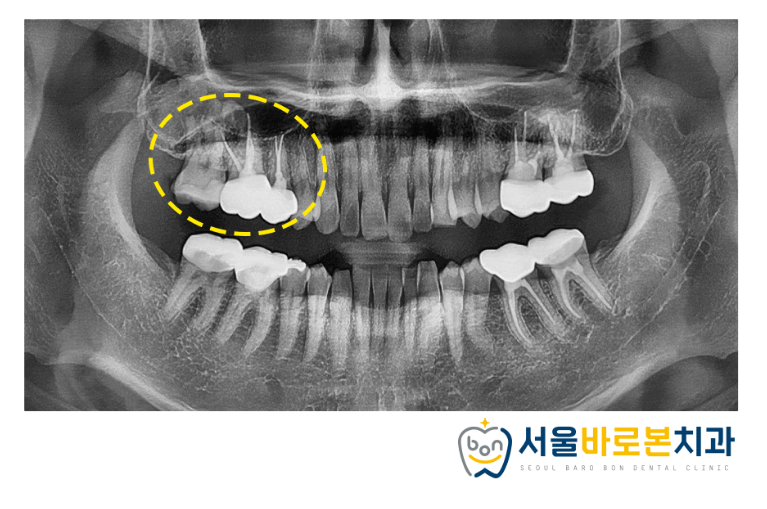

보철물까지 씌워 마무리했습니다.

이제 상하좌우 큰 어금니 부위는

거의 크라운을 씌우게 되었는데요.

이런 상태일수록 더욱

구강 검진은 필수라고 할 수 있습니다.